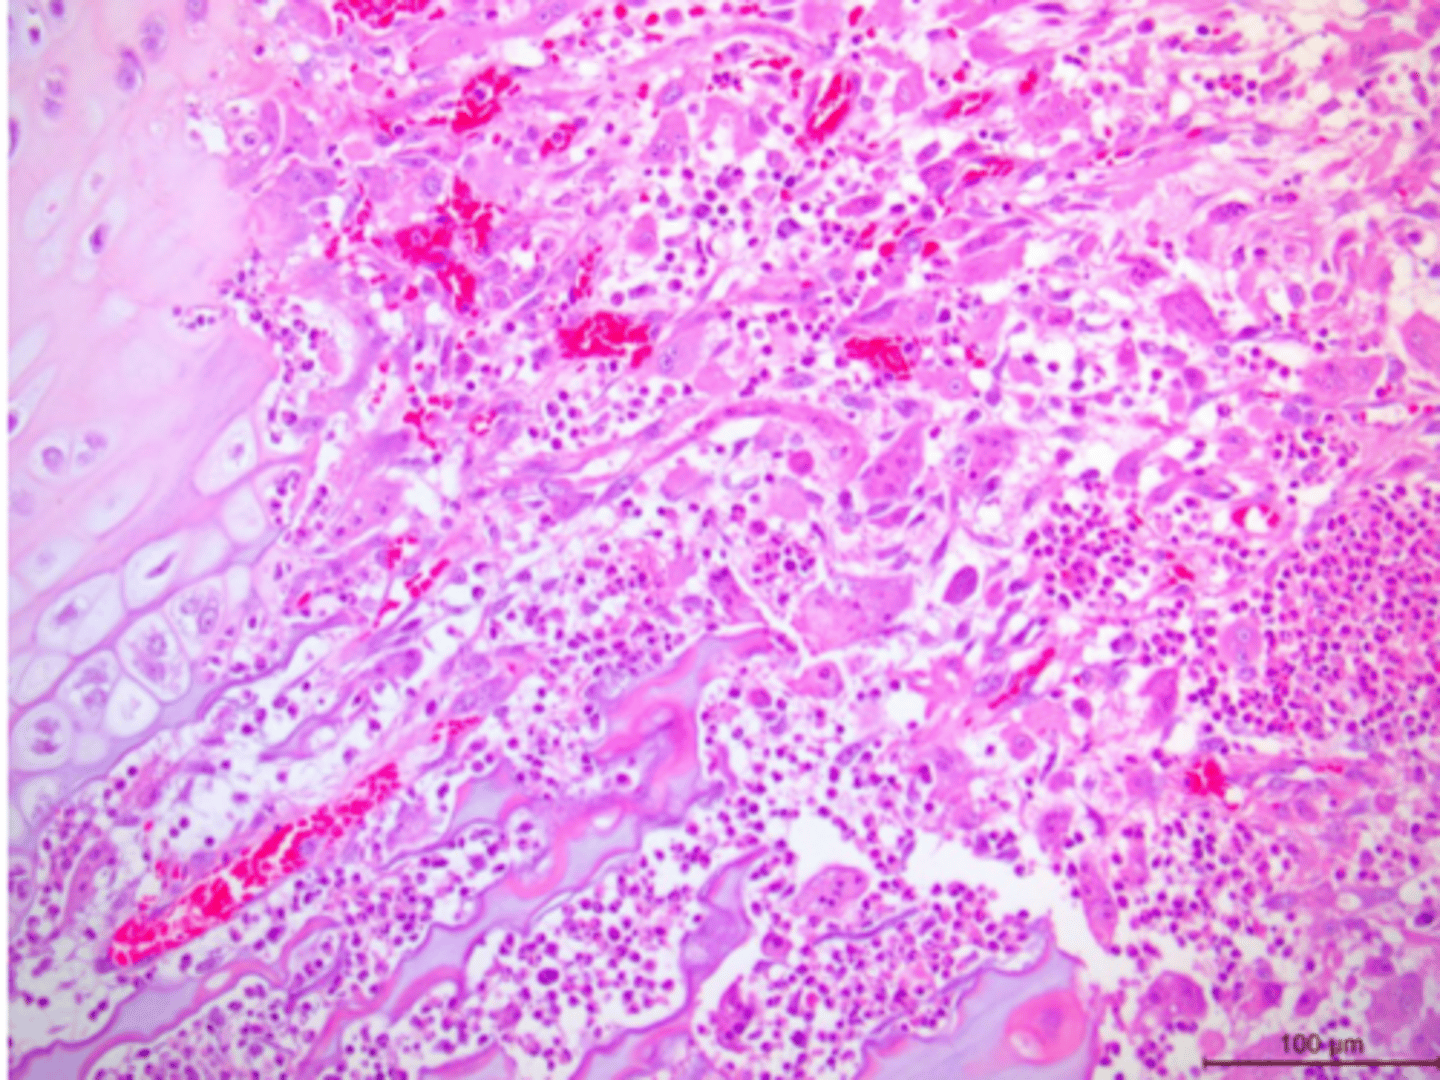

Identify the pathology:

Osteomyelitis